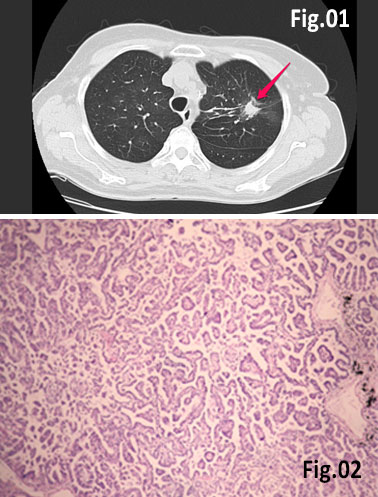

GISTs are rare mesenchymal neoplasms of the digestive tract [1,2]. They have been documented in all parts of the gastrointestinal tract, but are most common in the stomach and small intestine, followed by colo-rectum, mesentery, and esophagus [1,2]. However, the synchronous occurrence of lung cancer and GIST is extremely rare [3]. The incidence of GIST coexisting with additional malignancies is 9% to 27%, and primary lung cancer in GIST patients is 0.5%-1.2% [3]. A 75 year old woman with a smoking history for >30 years was diagnosed with advanced stage of left lung primary adenocarcinoma by chest computed tomography (CT) and bronchoscopy with sampling in February 2015 (Fig.1, Fig.2). The patient started Erlotinib 150 mg/day. In September 2015 the patient was admitted with vague abdominal pain and postprandial vomiting. Physical examination, routine blood, urine and stool investigations were unremarkable. Abdominal ultrasound detected an oval, homogenous, hypoechoic lesion 6/5/4 cm, arising from the submucosal layers of the gastric wall (Fig 3). The color Doppler demonstrated neovascularization (Fig 4). Except for 3 small simple liver cysts, no other abnormalities were present. Upper endoscopy and endoscopic ultrasound (EUS) revealed a large oval, slightly lobulated mass, hypoechoic 6x5cm between incisura angulars and greater curvature of the gastric body, originating from the 4th layer of the wall (muscularis propria). The tumor was slightly “dumbbell” shaped, protruding in and outside the stomach lumen, with several irregular hypoechoic zones and micro cysts within, looked encapsulated without infiltration of the surrounding tissues and pathologic abdominal lymph nodes (Fig. 5). A contrast-enhanced ulstrasound (CEUS) and contrast-enhanced computed tomography (CECT) of the abdomen additionally characterized the lesion and excluded liver metastases. (Fig. 6, Fig. 7) Percutaneous true-cut biopsy of the lesion was performed (18G, two separate puncture sites) (Fig 8). The immunohistochemical analysis revealed epithelioid-type GIST, diffusely positive for c-kit (CD117), with a weak focal expression of S-100 (Fig. 9). Due to life expectancy defined by the unresectable advanced lung cancer, the patient was not indicated for resection of the gastric GIST. Imatinib (Glivec) 400 mg/day was started as a “co-therapy” to Erlotinib in November 2015. After 12 months of co-treatment, a good control of both tumors was achieved. CT and abdominal ultrasound showed the gastric lesion was slightly shrunk on therapy, with large central necrosis (Fig. 10). The patient is being followed up.

Figure 2: Histology of the pulmonary adenocarcinoma